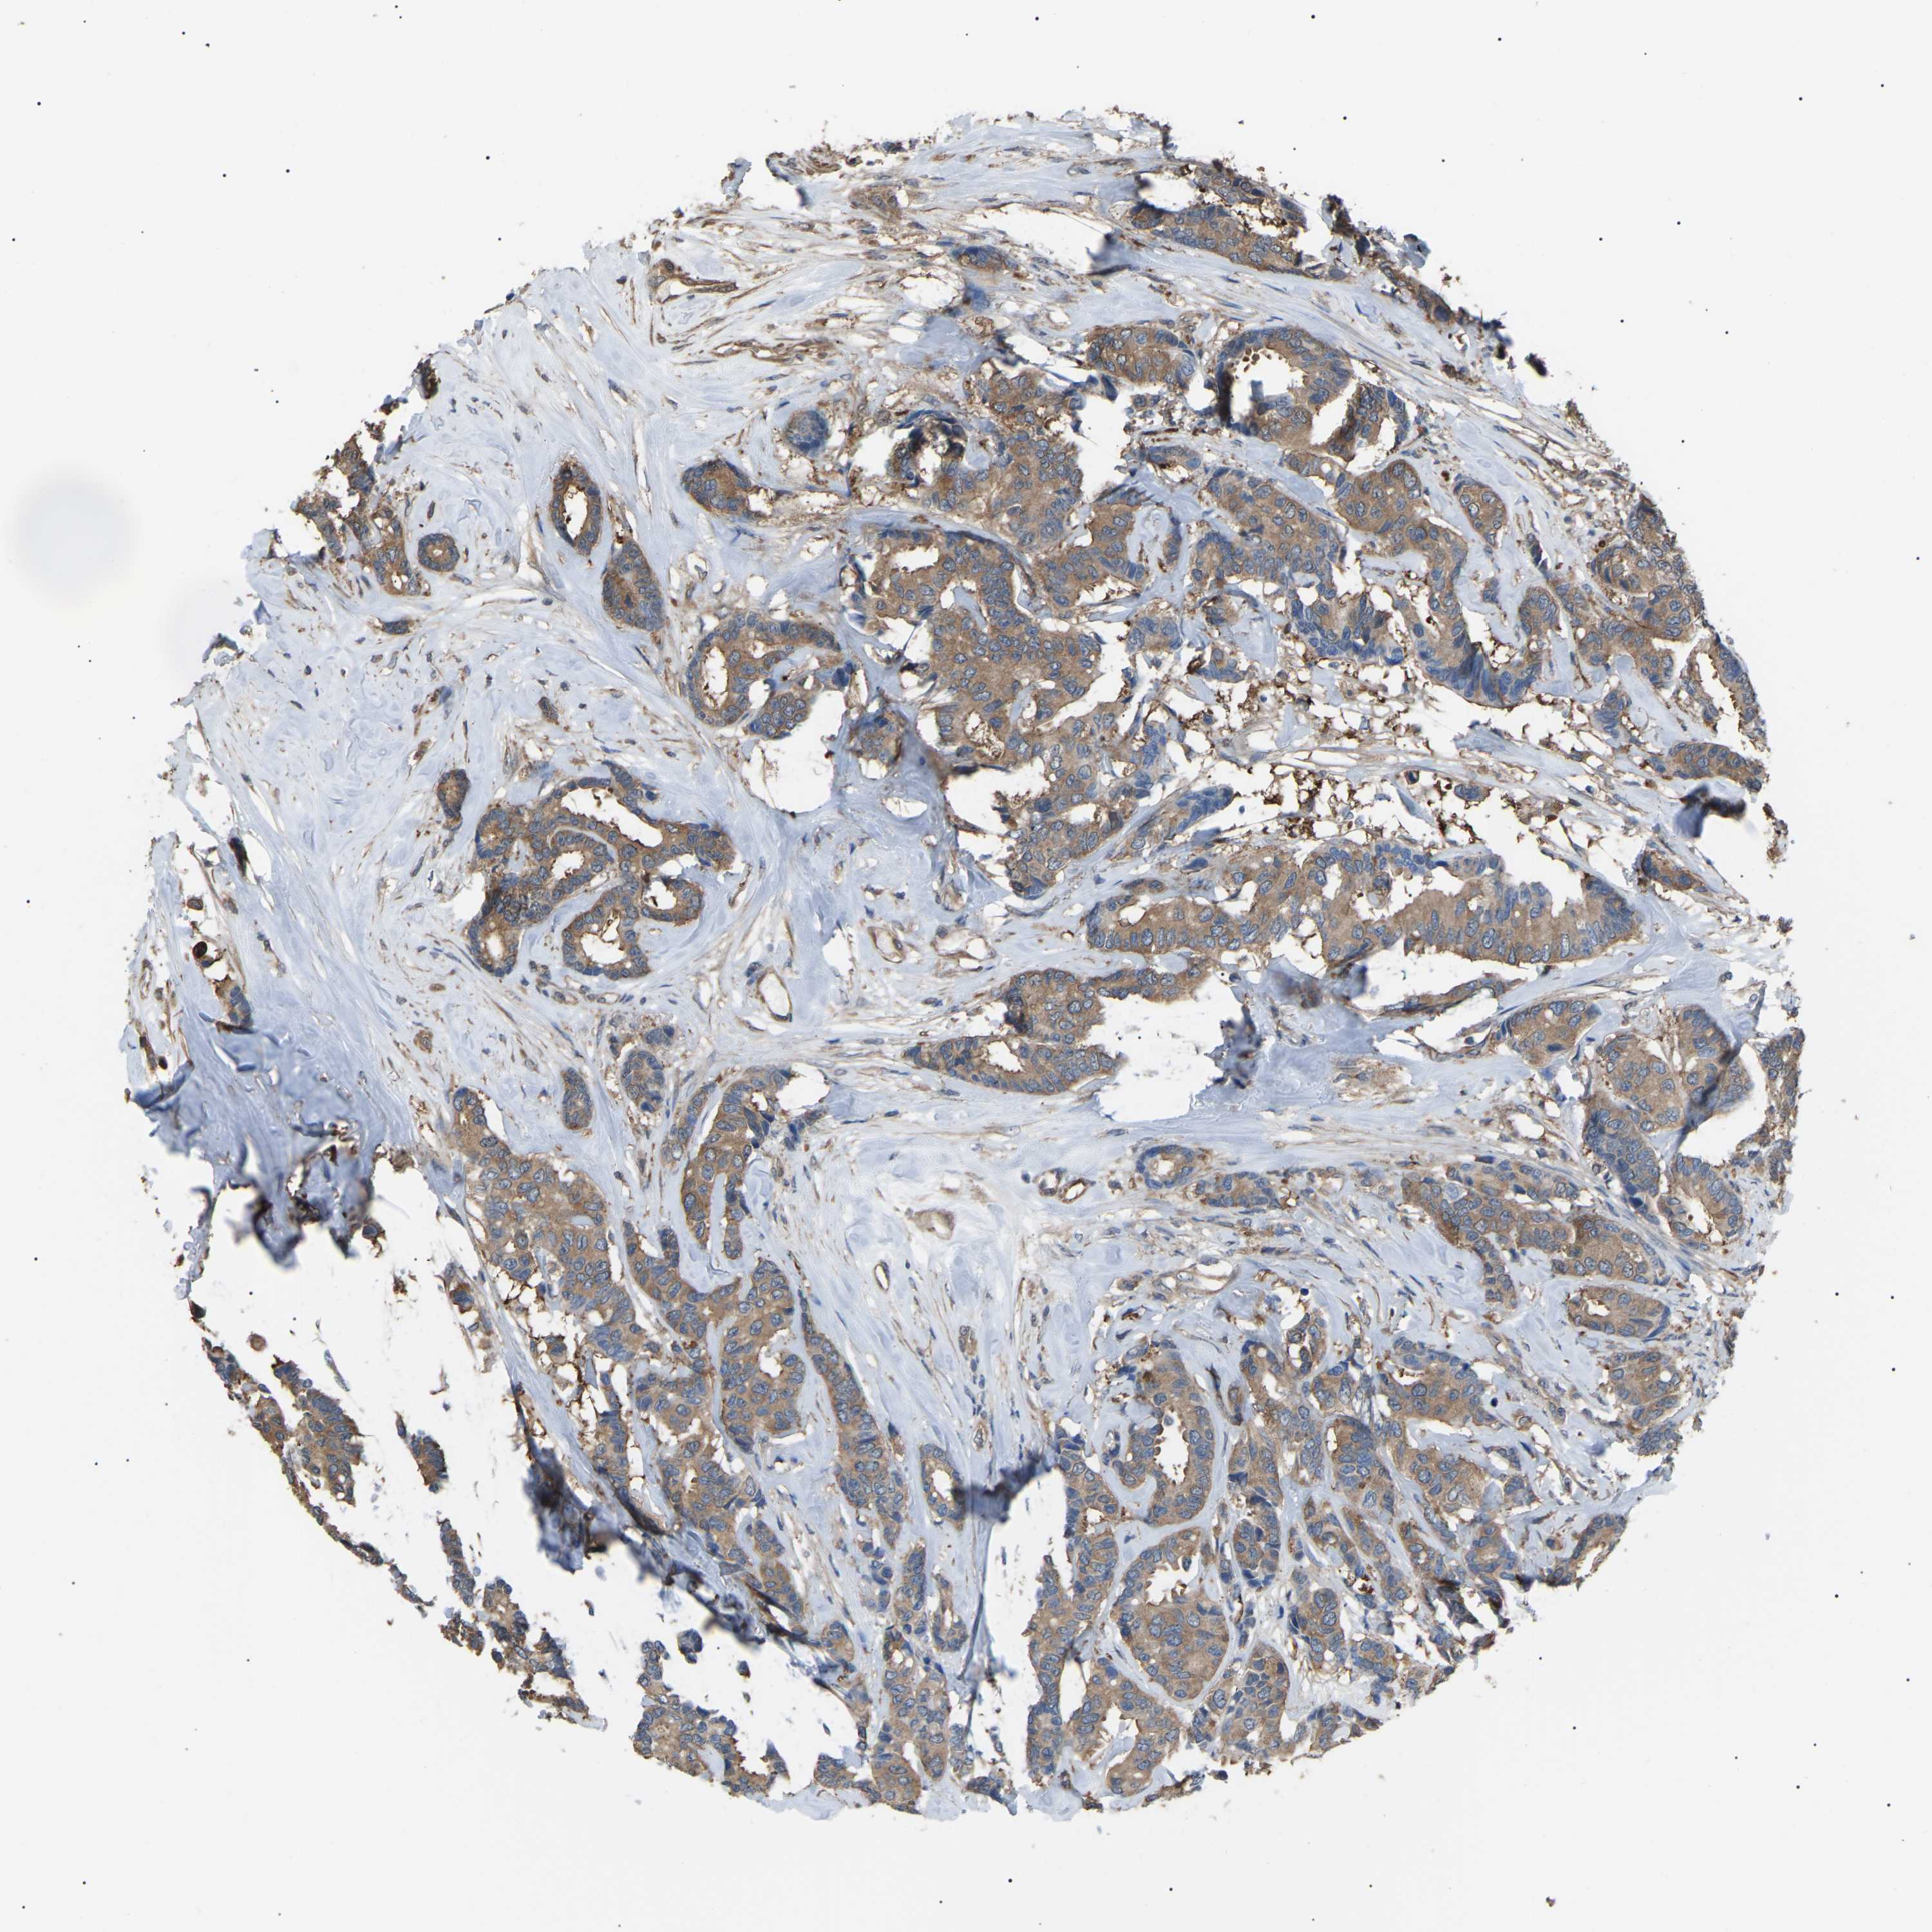

CANCER BREAST CANCER Show tissue menu

BRCA TCGA BRCA VALIDATION PROTEIN EXPRESSION

ANTIBODIES

AND

VALIDATION